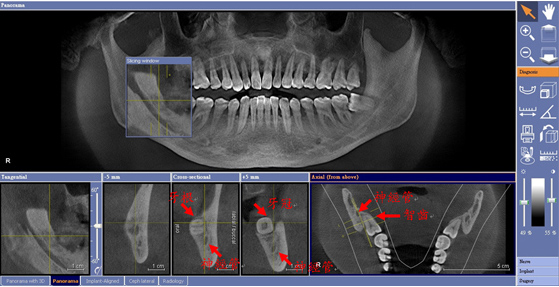

檢測智齒與神經管是否重疊